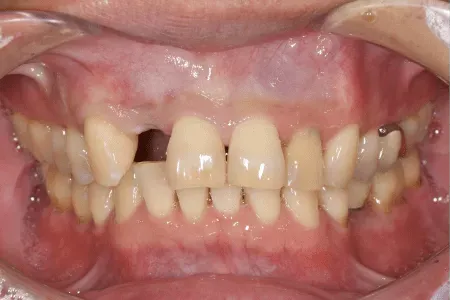

| 治療内容 | 前歯へのインプラント治療 |

|---|---|

| 治療期間 | 6か月 |

| 治療費用 | 43万円(税抜) |

| 副作用・リスク | 外科処置が伴うため、術後の疼痛・腫脹・出血・咬合痛などを生じる事があります。 麻酔を行う場合、腫れやむくみを生じる事があります。 また、被せ物や土台が外れたり、欠けたり、緩んだりする事があります。 |